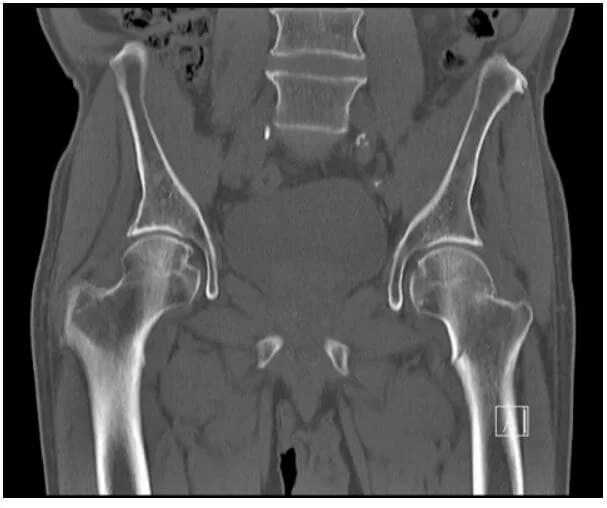

Мрт или кт тазобедренных суставов что лучше